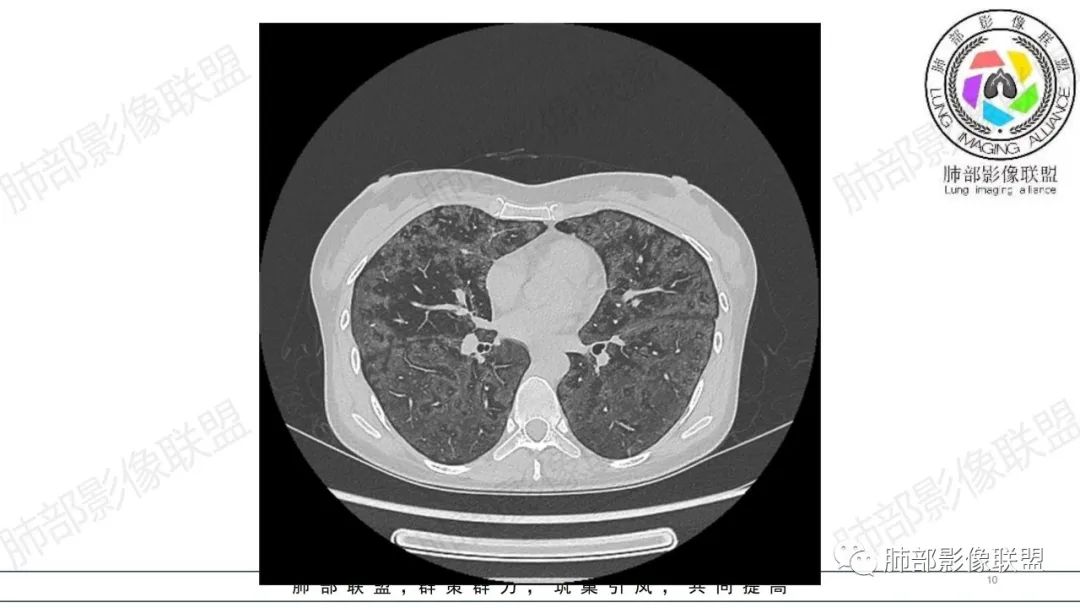

影像资料

34岁女性患者,“哮喘”病史30年,近期有可疑刺激性气体吸入史;因乏力半年,咳嗽、憋气、发热4天就诊;6.1CT提示双肺广泛毛玻璃影及粟粒样结节,胸膜下闲置及血管周闲置,可见树丫征,部分小叶间隔增厚。考虑:1.过敏性肺泡炎,有可疑刺激气体接触史,胸膜下闲置,广泛毛玻璃影,地图样分布,粟粒结节边界模糊,支持过敏性肺泡炎,但糖皮激素治疗效果不佳,且动态复查血常规血红蛋白进行性降低,过敏性肺泡炎 不符合;2.肺含铁血黄素沉积症:患者30“哮喘”病史,可能为肺含铁症状,肺部CT提示双肺弥漫毛玻璃影及粟粒结节影,中下肺明显,肺底部分小叶间隔增厚,近期咳嗽、憋气、发热,血常规血红蛋白进行性下降,考虑肺含铁急性期症状,但临床无咯血症状,肺含铁不典型。综合考虑:肺含铁血黄素沉积症>过敏性肺泡炎。

年轻女性 ,急性喘息发热,肺部影像弥漫磨玻璃密度,部分细小腺泡结节,胸膜下黑线显示,短期复查,病变密度增高,下肺明显,血管周围肺组织累及较少、且逐渐成小叶间隔分布。考虑弥漫肺泡内病变,并经淋巴道转移,下肺比上肺明显,多为免疫细胞功能下肺较强。1.过敏性肺泡炎,有相关病史,三层密度特点、头尾测分布,符合。2 肺泡微石症,多有钙化,且缓慢起病,病程不太符合,放待排。3 吸入相关肺损伤,有病史,疾病演变过程也符合渗出-肉芽肿改变,建议详细询问病史。4 感染性病变,结核?病变气道分布为主,如此弥漫且没有树丫不符合。5.巨细胞病毒,可以磨玻璃 结节 改变,没有免疫缺陷病史。最后考虑吸入所致 1过敏性肺泡炎、吸入性肺损伤 鉴别肺泡微石症。

肺内气腔磨玻璃结节,肝脾肿大,治疗后间质改变,弥漫大B可能